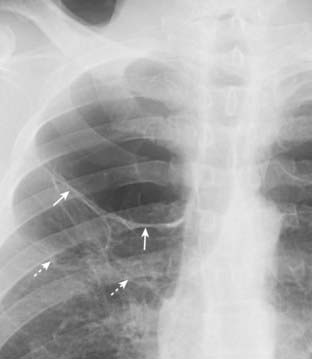

Figure 8-1 Visceral pleural line in a pneumothorax.

You must see the visceral pleural line to make the definitive diagnosis of a pneumothorax (solid white arrows). The visceral and parietal pleurae are normally not visible, both normally lying adjacent to the lateral chest wall. When air enters the pleural space, the visceral pleura retracts toward the hilum along with the collapsing lung and becomes visible as a very thin, white line with air outlining it on either side. Notice how the contour of the pneumothorax parallels the curvature of the adjacent chest wall.